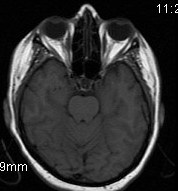

Zugrunde liegt eine chronische granulomatöse Entzündung im Bereich der sogenannten Orbitaspitze oder hinter der Orbita (Augenhöhle) in der Umgebung der Fissura orbitalis superior oder des Sinus cavernosus, einem Netz venöser Blutgefäße. Die Ursache dieser Entzündung ist unbekannt. Zur Behandlung werden Kortikoide eingesetzt. Die Prognose ist günstig, spontane Remissionen sind möglich; es können jedoch auch Rezidive auftreten. Die Diagnose erfordert den sicheren Ausschluss möglicher anderer Erkrankungen, die mit einer ähnlichen Symptomatik einhergehen können, etwa Tumoren, Traumen oder ein Aneurysma. Eine bildgebende Diagnostik ist daher in jedem Fall erforderlich.